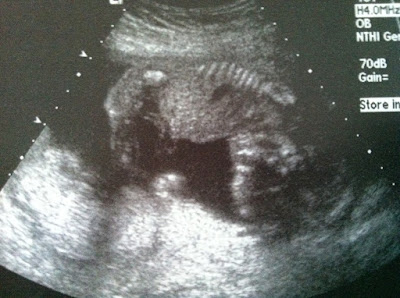

![]() |

| She is flipped upside down, arched, and has her chin on chest…see it? Ha! |